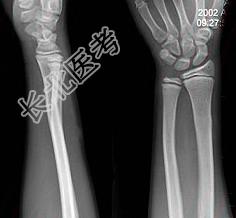

- 单项选择题患者男性,10岁, 外伤后感患处疼痛,根据所提供图像, 选择最佳选项 ( )

A、骺移骨折

B、踝关节脱位

C、腕关节脱位

D、未见异常

E、青枝骨折